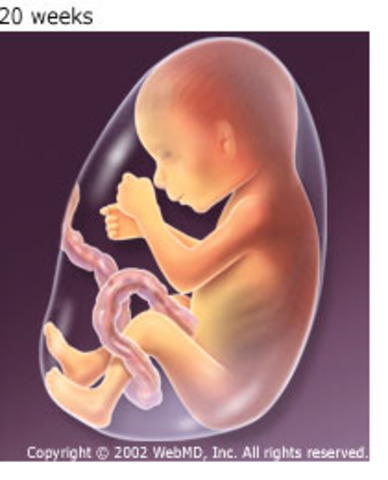

• Week 20

Week 20

Your baby weighs about 10 1/2 ounces now. He's also around 6 1/2 inches long from head to bottom and about 10 inches from head to heel — the length of a banana. (For the first 20 weeks, when a baby's legs are curled up against his torso and hard to measure, measurements are taken from the top of his head to his bottom — the "crown to rump" measurement http://www.babycenter.com/6_your-pregnancy-20-weeks_1109.bc